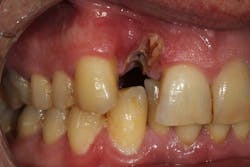

These alveolar bone changes often compromise implant placement due to thin bone volume (figures 2a–2d).

Reduction in quantity and quality of bone can also compromise functional and esthetic outcomes of both implants and fixed bridge restorations (figures 3 and 3a).